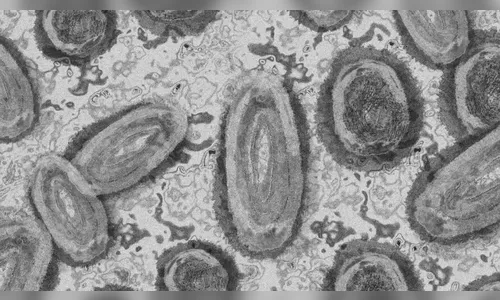

Conheça os sintomas da varíola dos macacos e saiba como se proteger

O número de casos da varíola dos macacos está crescendo no mundo todo e, por conta disso, mais informações sobre a doença, também conhecida como monkeypox, como os sintomas e como se proteger dela, estão sendo divulgadas.